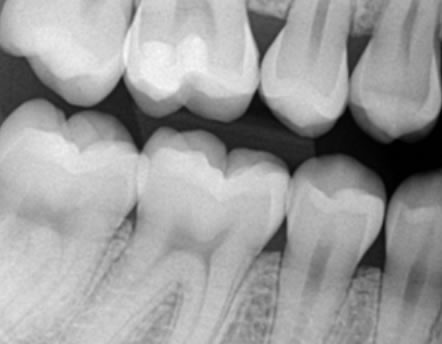

Bitewing snimka zubi - To je snimka stražnjih gornjih i donjih zuba, koristi se za detekciju početnog karijesa između stražnjih zubi.

Početni karijes između zubi se teško dijagnosticira prilikom kliničkog pregleda pa je preporučljivo napraviti ovu snimku za detekciju karijesa.